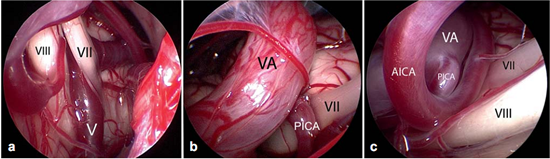

面神经的微血管减压术是治愈面肌痉挛的唯一治疗选择。手术旨在去除出脑干区(REZ)血管对神经的压迫。血管对神经造成压迫是主要病因。手术需全身麻醉。为了观察手术过程中耳蜗的和面部的神经的改变,需要在手术进行过程中对面神经的肌电图(EMG)和听觉诱发电位(auditory evoked potentials)进行监测。使用乙状窦后入路开颅术(retrosigmoidal craniotomy)(figure 3)暴露小脑桥脑角。在随后的手术过程中,尤其注意检查出脑干区的面神经(figure 5),该面神经发源于脑干。内窥镜检查法对于确定血管压迫位置很有效(figure 4,6)。因此,在尊龙凯龙时医院把内窥镜检查法作为指导程序。

Figure 6不同类型的血管压迫。Ⅶ=面神经;Ⅷ=蜗神经

a:由靠近脑干的静脉(Ⅴ)所造成的压迫;

b:椎动脉(VA)和小脑右下动脉(PICA)共同压迫;

c:椎动脉(VA)、下移的小脑右下动脉(PICA)和小脑前下动脉(AICA)共同压迫。